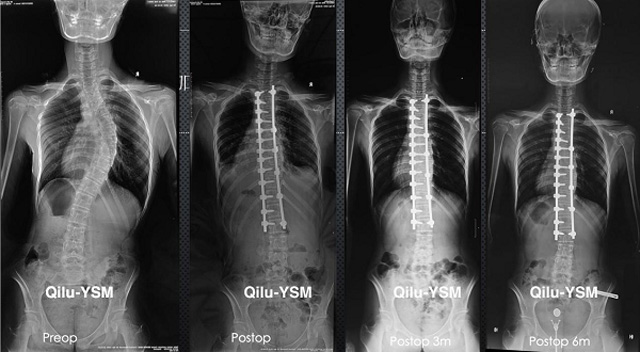

懸吊DR-全電動型機架DR檢查主要用于胸部、四肢、關節、脊柱等,主要檢查肺部炎癥、腫瘤、結核病、四肢骨關節的骨折、四肢關節、脊柱外傷等。DR就是X光,是一種數碼影像,曝光時間很短,攝像量很小,影像質量也很好,可以說是一種替代CR的方法。DR檢查有其局限性,需要做CT平掃等檢查,周圍淋巴結的轉移以確定病變的良惡性、范圍、大小、與鄰近組織的關系。